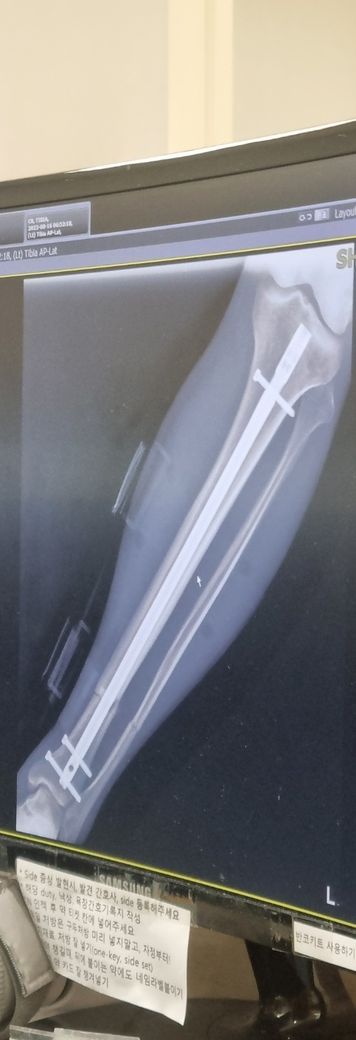

경골, 비골 모두 골절 되었고 경골만 금속정으로 고정했습니다.

(아래 사진은 삽입한 금속정 사진으로 수술 받은지 얼마 안되었을 때 입니다. 현재는 거의 유합 되었습니다.)